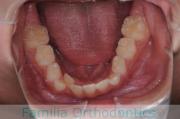

下の歯並びを綺麗にしたいということで来院されました。マウスピース型矯正装置のひとつ、インビザライン/Invisalign®(薬機法および医薬品副作用被害救済制度の対象外)を用いて治療しました。

非抜歯で1年半、20回程度の通院で完了しています。

下顎

前歯の関係など